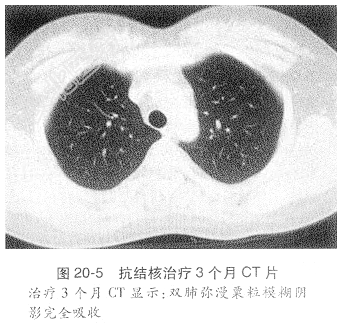

患者入院时查体:体温38.9℃,脉搏110次/min,呼吸23次/min。神志清楚,皮肤、巩膜无黄染,双侧颈部未扪及肿大淋巴结。双肺呼吸运动对称,双肺呼吸音稍粗,未闻及干湿啰音。心率110次/min,律齐,未闻及杂音。腹软,无压痛及反跳痛,肝脾肋下未及,神经系统体征阴性。辅助检查示:血气分析示pH7.45,二氧化碳分压27.9mmHg,氧分压159mmHg,氧饱和度99.3%。血沉35mm/h,C-反应蛋白10mg/L,血结核抗体阴性,血T-SPOT检查A抗原30,B抗原50。血白细胞总数正常。痰浓缩找抗酸杆菌3次阴性,痰荧光双标记定量结核分枝杆菌阴性。血生化示肝肾功能正常。胸CT示双肺弥漫粟粒模糊阴影(图20-4)。腰穿查脑脊液示糖2.9mmol/L、氯化物118mmol/L、ADA1.4U/L、蛋白945mg/L、白细胞5.0×10⁹/L;头颅MR示颅内多发结节空洞样病灶。根据患者以上检查结果诊断为急性血行播散性肺结核;结核性脑膜炎伴颅内多发结核瘤,给予加强抗结核治疗及激素治疗,同时降颅压等对症治疗。待临床症状明显改善后,激素逐渐减量至停用,治疗3个月后复查胸CT示双肺弥漫性病灶基本吸收(图20-5)。复查腰穿查脑脊液化验结果示糖4.0mmol/L、氯化物122mmol/L、ADA1.0U/L、蛋白294mg/L、白细胞5.0较前明显好转。